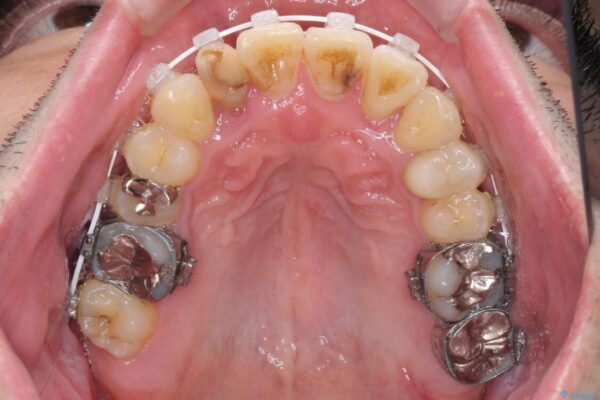

治療途中

• 割れてしまった奥歯とデコボコの前歯 矯正治療とインプラント治療 治療途中画像